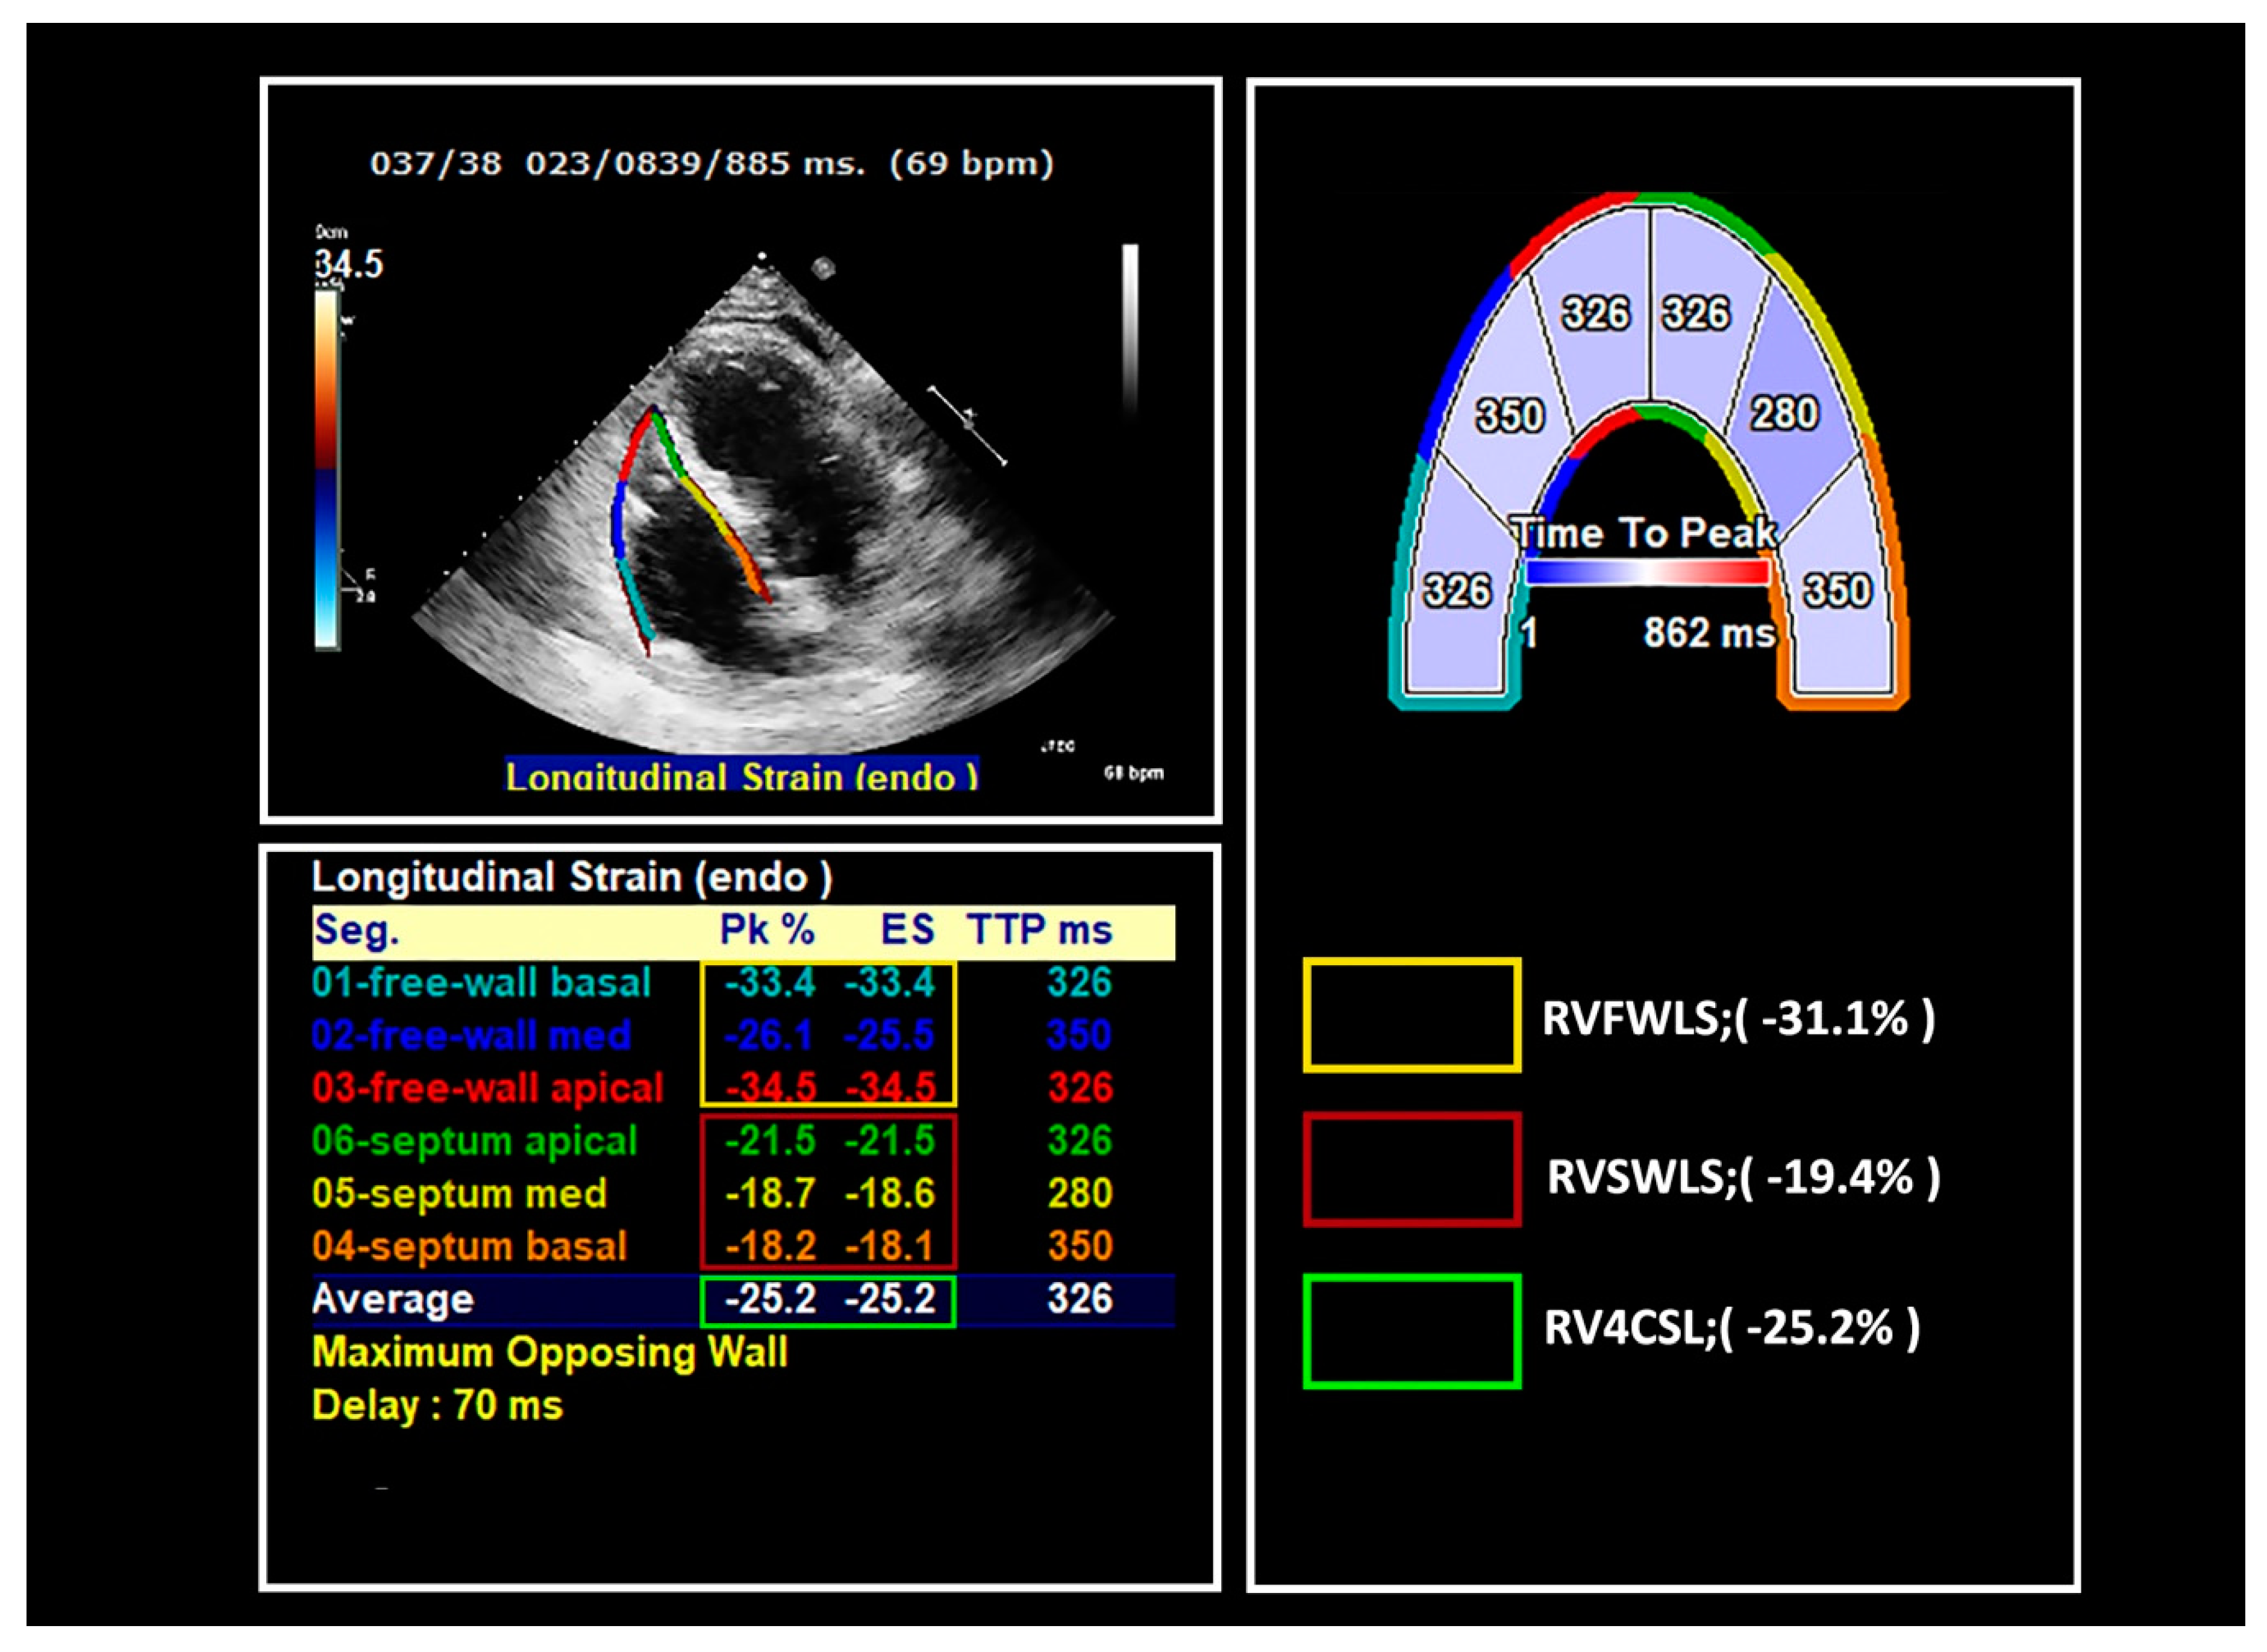

7. Right Ventricle Strain